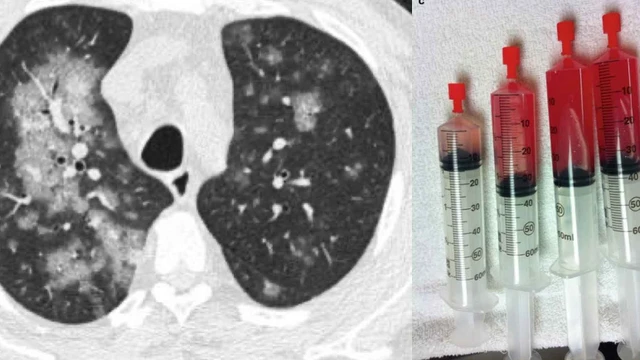

:format(webp)/xuat_huyet_phe_nang_lan_toa_1_2b195a06dc.jpg)

Xuất huyết phế nang lan tỏa (Diffuse Alveolar Hemorrhage - DAH) là một trường hợp cấp cứu y tế và đe dọa tính mạng có thể do nhiều rối loạn gây ra. Bệnh có biểu hiện là ho ra máu, thiếu máu và thâm nhiễm phế nang lan tỏa. Nhận biết sớm tình trạng bệnh là rất quan trọng, bởi vì chẩn đoán và điều trị kịp thời rất cần thiết để ngăn ngừa biến chứng tử vong.